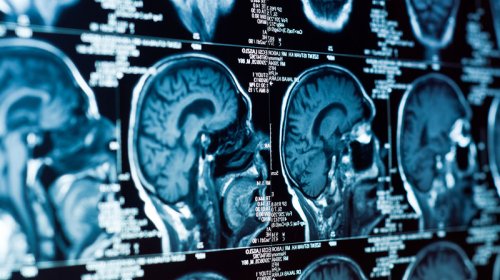

Pensilvaniya Universitetinin alimləri müəyyən ediblər ki, stress beyin qan dövranında pozuntular yarada bilər. Bu faktor Altsheymer xəstəliyinin inkişafına səbəb ola bilər.

Alimlər aşkar ediblər ki, siçanlarda normal qan dövranını təmin edən və neyronların koordinasiyalı fəaliyyətinə cavabdeh nadir sinir hüceyrələri — nNOS tip 1 neyronlarıdır. Bu hüceyrələr bütün beyin neyronlarının 1%-dən azını təşkil edir. Onlar stressə son dərəcə həssasdır və güclü emosional yüklənmələr zamanı ölə bilərlər.

nNOS hüceyrələrinin təsirini öyrənmək üçün alimlər saporin toksinindən istifadə edərək yalnız bu tip neyronları selektiv şəkildə məhv ediblər. Təsir sonrası beyin damarlarının spontan dalğalanmalarında əhəmiyyətli zəifləmə və neyron fəaliyyətində azalma müşahidə olunub.

Həmçinin, heyvanlarda bu neyronların məhv edilməsi qan dövranı və beyin elektrik fəaliyyətinin azalmasına səbəb olub, xüsusilə yuxu zamanı. Alimlərin sözlərinə görə, bu nNOS hüceyrələrinin beyinə oksigen təmin etmədə və neyron əlaqələrinin saxlanmasında əsas rol oynadığını sübut edir.

“Qan dövranının azalması beynin funksiyasının pisləşməsini və nevrodegenerativ xəstəliklərin inkişafını sürətləndirən amillərdən biridir. Xroniki stress səbəbindən bu nadir neyronların itirilməsi bu pisləşmənin az qiymətləndirilmiş səbəbi ola bilər", deyə tədqiqatın baş müəllifi, mühəndislik elmləri professoru Patrick Drev qeyd edib.

Alimlər hesab edirlər ki, oxşar funksiyalı hüceyrələr insan beynində də mövcuddur. Onların rolunu başa düşmək, yaşa bağlı beyin pozuntularının qarşısını almaq və bəlkə də demensiyanın inkişafını yavaşlatmaq üçün yeni yolların hazırlanmasına kömək edə bilər.